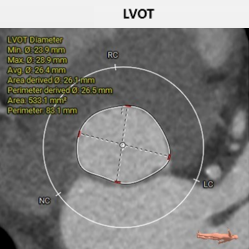

主动脉根部评估:

• 瓣环 周长79.7mm,平均周长径25.4mm

• LVOT 周长83.1mm,平均周长径 26.5mm